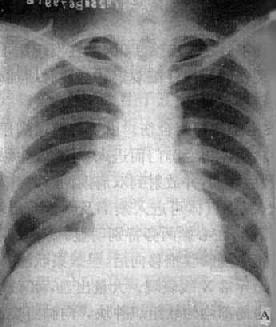

(1)一侧性肺不张:X线现为患侧肺野均匀致密,纵隔向患侧移位,肋间隙变窄(图3-1-7)。健侧肺可有代偿性肺气肿。

图3-1-7 一侧性肺不张

左侧支气管阻塞引起左侧全肺不张,显示左侧肺野均匀致密,

纵隔向患侧移位,肋间隙变窄,膈升高